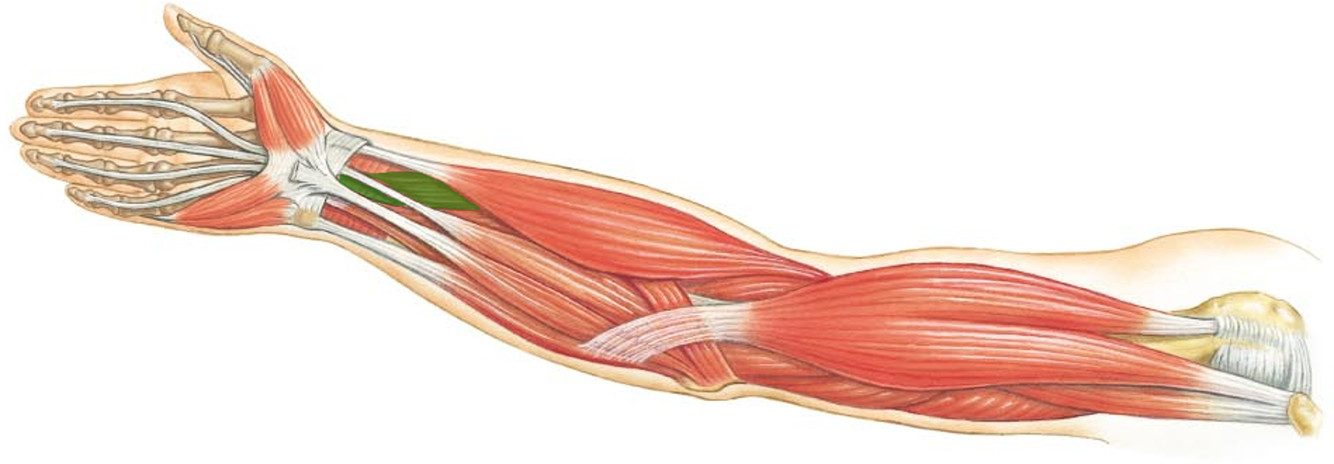

What is the innervation of this muscle?

Muscle - Flexor pollicus longus

Median nerve

C8 + T1

What is the innervation of this muscle?

Muscle - Pronator teres

Median nerve

Muscle - Flexor carpi radialis

Median nerve

Muscle - Palmaris longus

Median nerve

Muscle - Flexor digitorum superficialis

Median nerve

C7 - T1